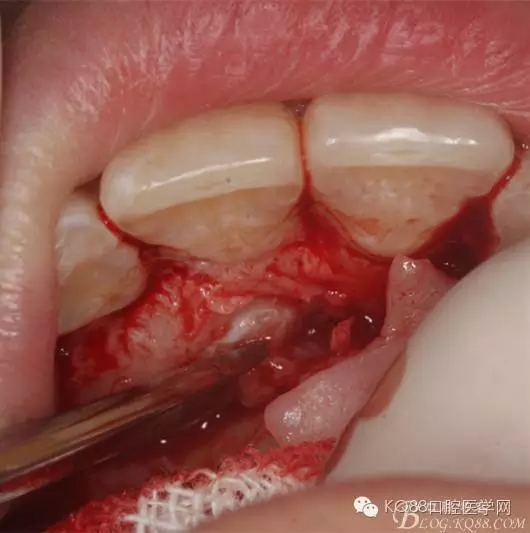

圖6.局部無痛麻醉、行唇側(cè)弧形切口

圖7.高速渦輪機(jī)去骨

圖7暴露埋伏的13牙冠

圖8.高速牙鉆橫斷13牙冠。比哦那個(gè)用牙挺分別挺出牙冠和牙根